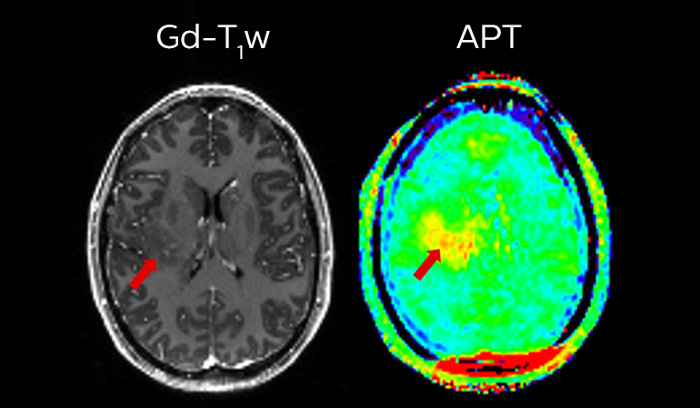

2 Definitive is defined as features that are expected to deliver alternative contrasts, functional or quantitative images

3 Compressed SENSE and APT are work in progress and not for sale in the USA

APT** and REACT**: The next steps towards non-invasive imaging strategies for pediatric MRI

Jeffrey H. Miller, MD

Vice Chair of Radiology for Research and Academic Affairs, Phoenix Children’s Hospital, Phoenix, AZ, USA